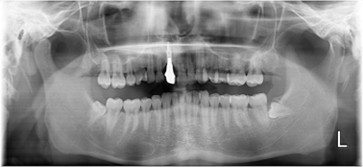

70代 女性

治療前

- 70代/女性

- 患者の具体的な症状

- 下顎の奥歯が義歯で噛みづらいため、インプラント治療を希望

- 検査方法

- コーンビームCT、レントゲン撮影

- 診断結果

- 左下6欠損

- 治療詳細

- 左下6インプラント埋入1本、骨造成なし、局所麻酔

- 通院回数

- 8回

- 治療期間

- 6か月